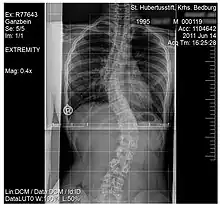

Scoliosis

.jpg)

Scoliosis, is a medical condition where a person's spine has several irregular curves that are located between the neck and the pelvis.[8] Symptoms of scoliosis in mild cases usually exhibit abnormal posture, back pain, tingling or numbness in the legs and in worse cases can exhibit breathing problems, fatigue, permanent deformities and in rare cases heart problems.[8]